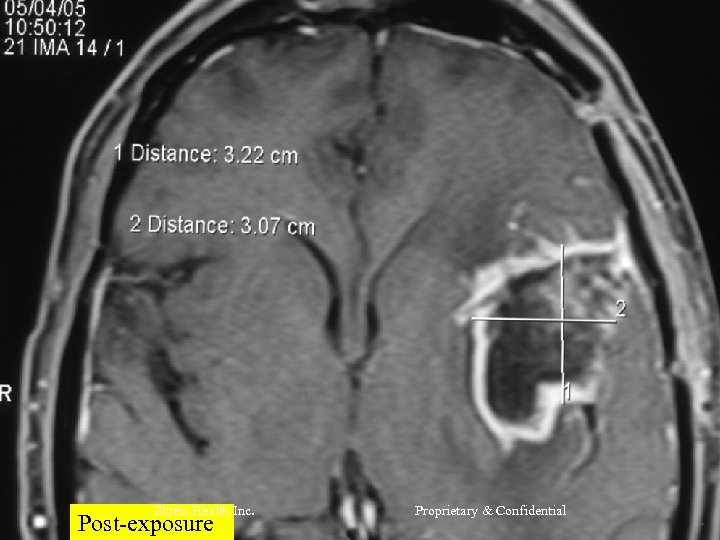

CASE 2 Mr R, 56 yrs l Nov 2004 – MRI Brain = Left frontal SOL (4 x 3 cm) - SX = Craniotomy x decompression of insular glioma HPR = Glioblastoma Grade IV l RT – 60 Gy/30 # till Jan 2005 l CT – Temedol x 2 # till Feb 2005 l Shreis Health Inc. Proprietary & Confidential

l l Presented Feb 05 - Loss of memory - Apathetic - Hemiparesis ® (power 3/5) Today after 1 course of RFQMR - No focal/Gen Neuro deficit - Normal higher functions and back to work. Shreis Health Inc. Proprietary & Confidential

Shreis Health Inc. Post-exposure Proprietary & Confidential

Shreis Health Post-exposure Inc. Proprietary & Confidential